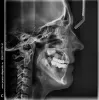

На нижней челюсти установлено два моста с обеих сторон, при этом правый нижний мост удаляется в связи с кистой опорного 47 зуба для последующей имплантации. При этом задействовать нижнюю челюсть в дальнейшем брекетами я не хочу. Трижды исправляла брекетами мезиальный прикус. Сейчас верхние зубы перекрывают нижние. Но верхняя челюсть заужена и есть дисфункция ВНЧС.

Возможно ли расширение верхней челюсти различными аппаратами притом, что на верхней челюсти с обеих сторон имеются уже два металлокерамических моста?

Нужен осмотр полости рта, качество изготовления мостовидных протезов, изучение моделей челюстей и снимков.

После комплексного обследования у стоматолога-ортодонта будет выбран метод лечения и его прогноз.